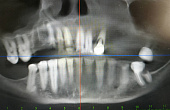

Основной профиль стоматологической клиники «Аладен» – имплантация.

Пациентам предлагают широкий выбор разнообразных линеек имплантов: от базовых израильских до швейцарских премиум-класса.

Высококвалифицированные специалисты с большим опытом работы берутся за самые сложные случаи. В клинике «Аладен» можно вернуть зубы при полной адентии за неделю.